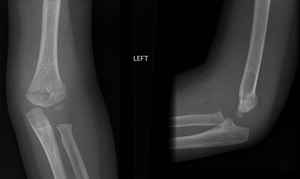

6. Look for obvious fracture lines on the AP view

|

Supracondylar fracture evident on the AP view |

Non-displaced supracondylar fracture

Supracondylar fracture with posterior angulation

Displaced supracondylar fracture